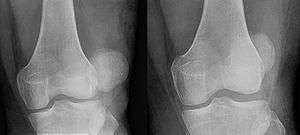

| Patella luxation on radiograph. Left before, right after reduction. After reduction the patella is still displaced. | |